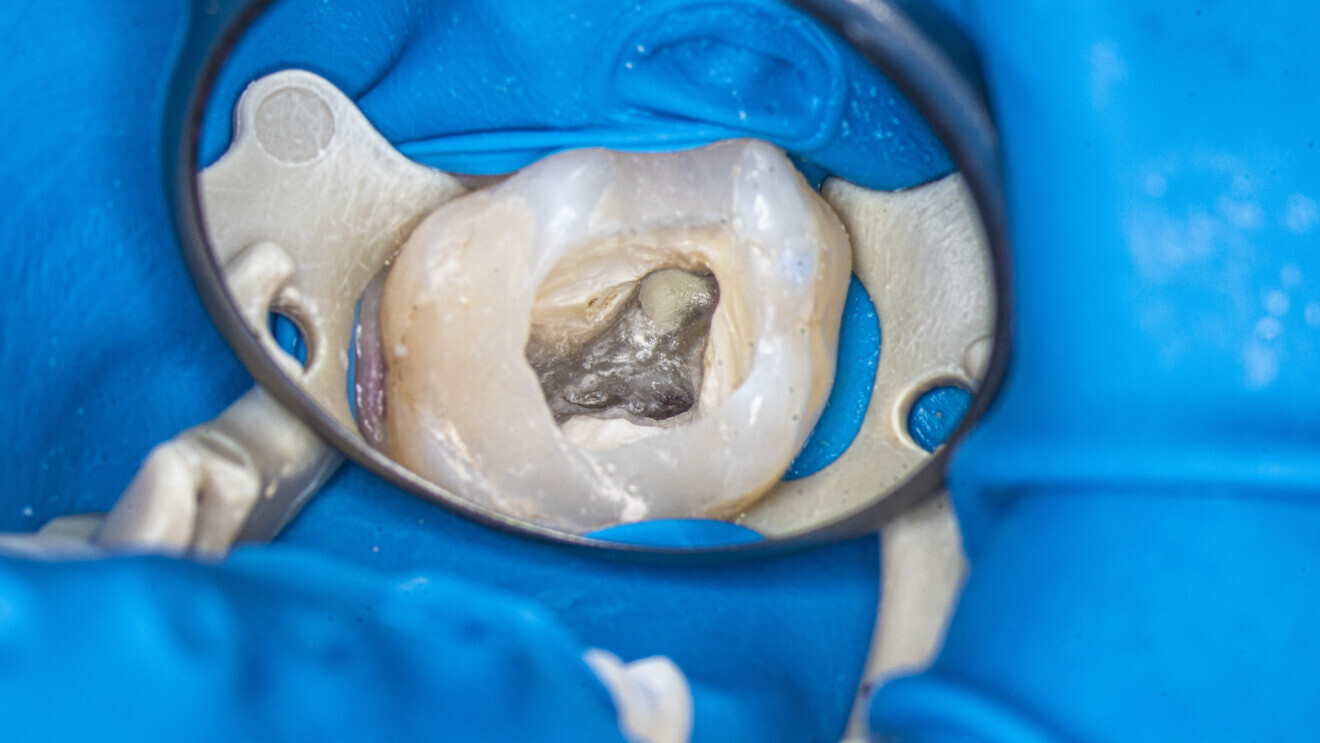

An access cavity had already been created by the referring dentist. During visualisation of the pulp chamber (Fig. 22), remnants of the pulp were identified. In order to properly identify canal orifices, cleaning of the pulp chamber was necessary. This is standard protocol for every endodontic treatment, and it is very important in order not to transport debris from the pulp chamber to canal space. This procedure was done using an Er,Cr:YSGG laser with a wavelength of 2,780 nm (Waterlase, BIOLASE) and RFPT5-10 tip (Fig. 23). After this procedure, which should be done according to the protocol of 1 minute of continuous activation and 1 minute of rest (Fig. 24), the operator can start the instrumentation protocol.

Fig. 21

Fig. 22